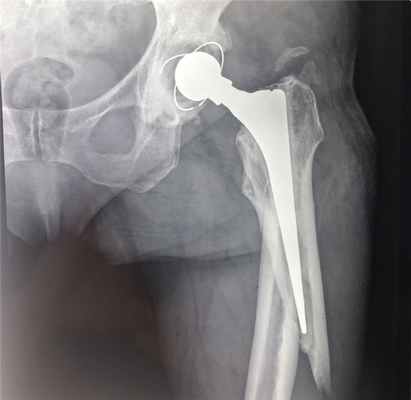

Вывихи бедренной кости в тазобедренном суставе (в т.ч. вывихи головки эндопротеза, эндопротезирование тазобедренного сустава, перипротезные переломы)

В случаях, когда тазобедренный сустав утрачивает свои функции (стирается гладкий хрящ, который обеспечивает легкоескольжение головки бедра в вертлужной впадине) и любые движения вызывают нестерпимую боль, пациентам проводят операцию эндопротезирования. Эндопротез – это искусственный заменитель какого-либо органа человека (выполняющий его функцию), который располагается внутри тела человека. Эндопротезирование тазобедренного сустава – это операция по замене пораженных компонентов сустава на эндопротез, который обладает анатомической формой здорового сустава и дает возможность осуществлять полный объём движений. Вывихи поле такой операции происходят весьма редко, но случаются, и в основном это вывихи головки эндопротеза.